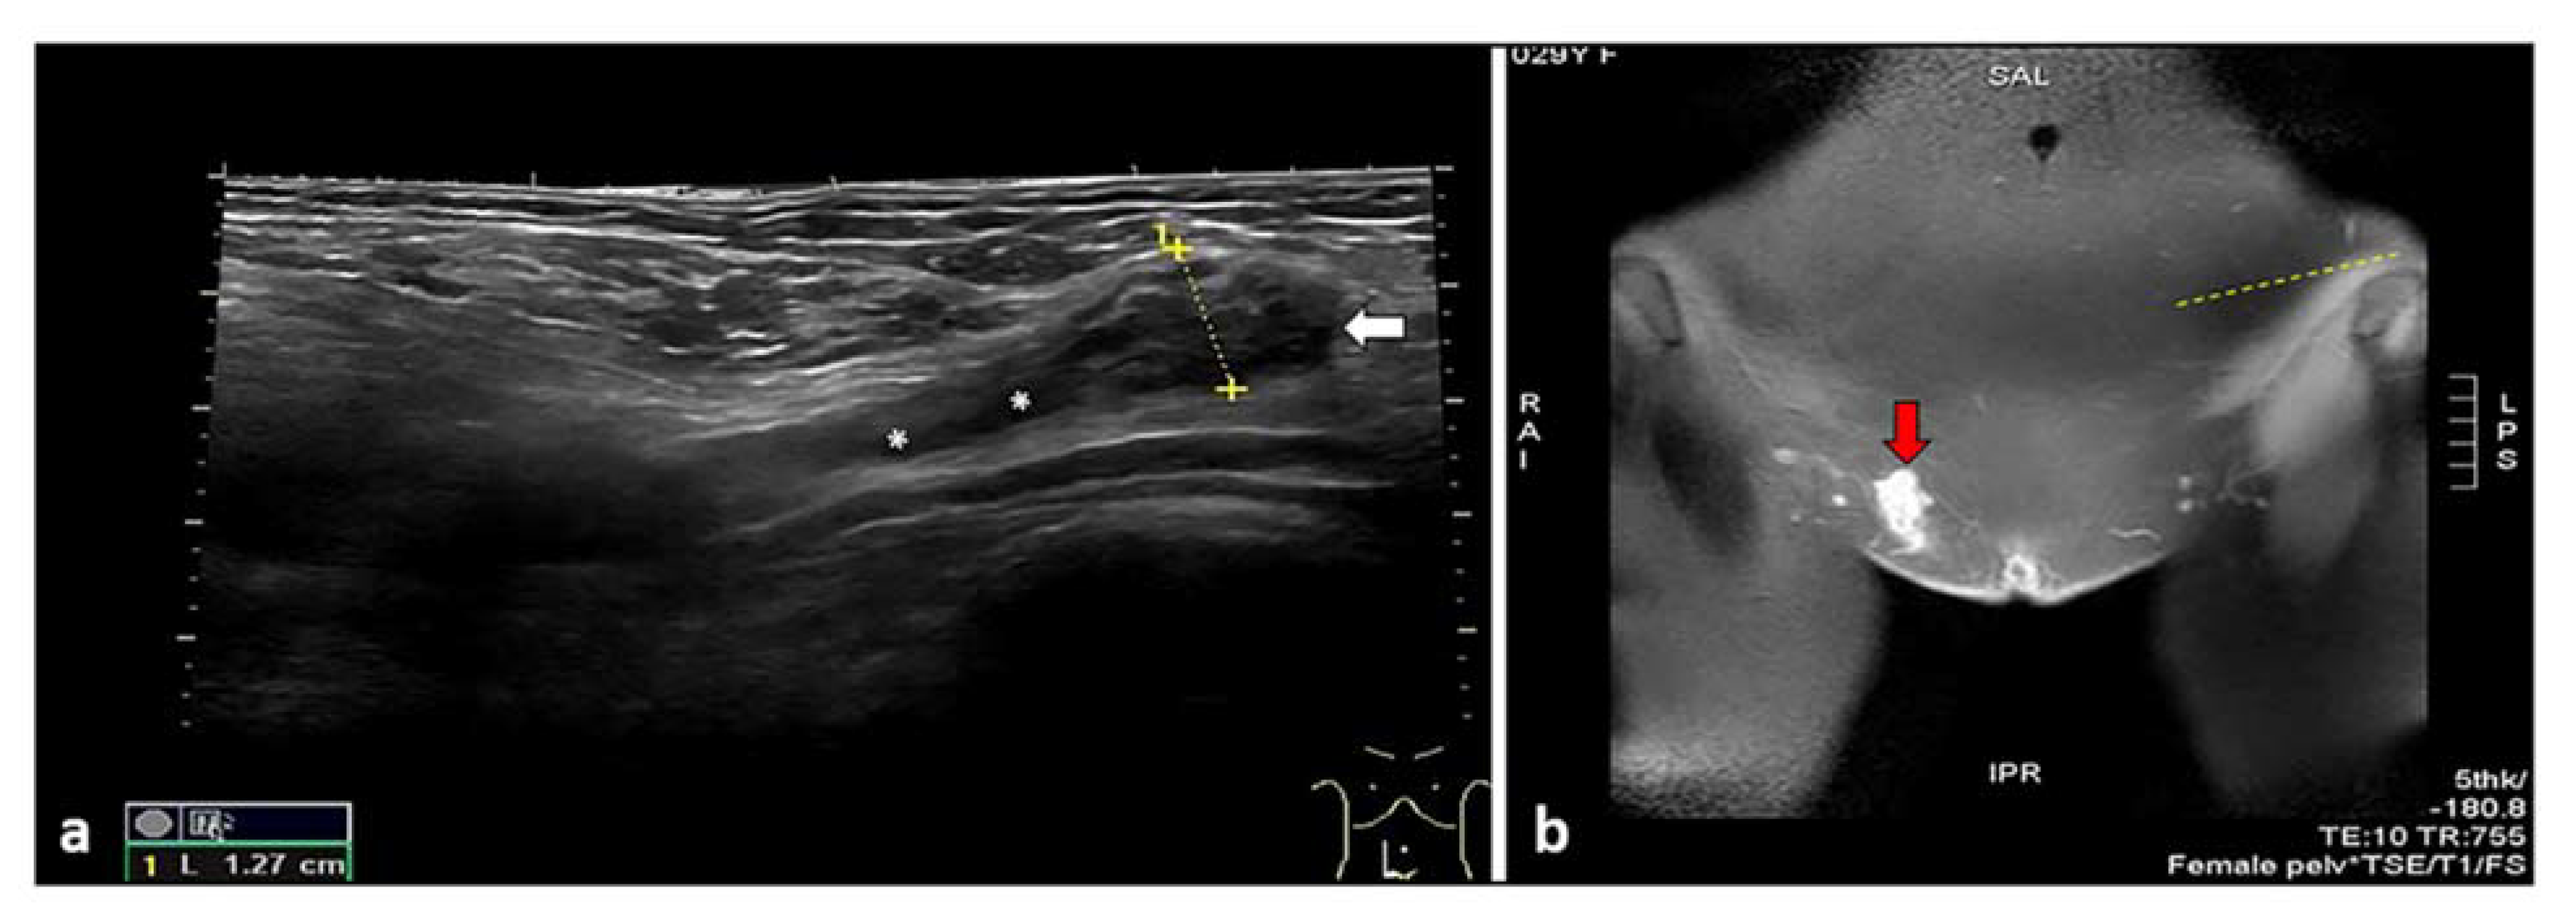

6. Inguinal Canal Endometriosis